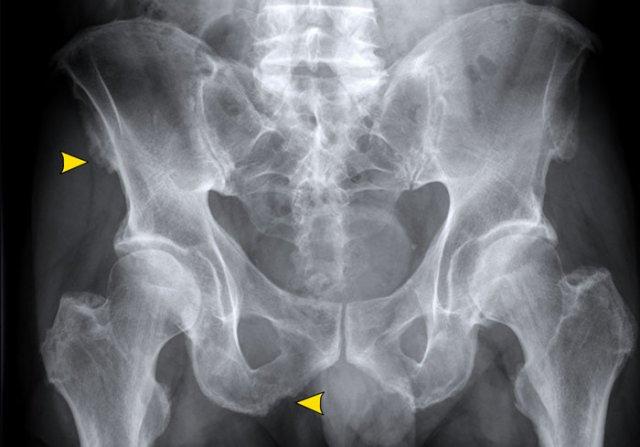

Hình ảnh của một bệnh nhân khác mắc DISH.

Có bệnh lý điểm bám gân tại mào chậu, ụ ngồi và mấu chuyển lớn.

Phần dưới của khớp cùng chậu bình thường (khác với viêm cột sống dính khớp).

Có cốt hóa dây chằng ở phần trên của khớp cùng chậu.